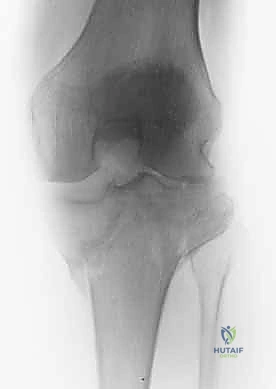

2. التصوير الإشعاعي (X-rays)

الخطوة الأولى هي التقاط صور أشعة سينية من عدة زوايا (أمامية خلفية، وجانبية). تعطي الأشعة السينية فكرة عامة عن وجود الكسر وموقعه، لكنها غير كافية لتقييم الكسور ثنائية اللقمة المعقدة.